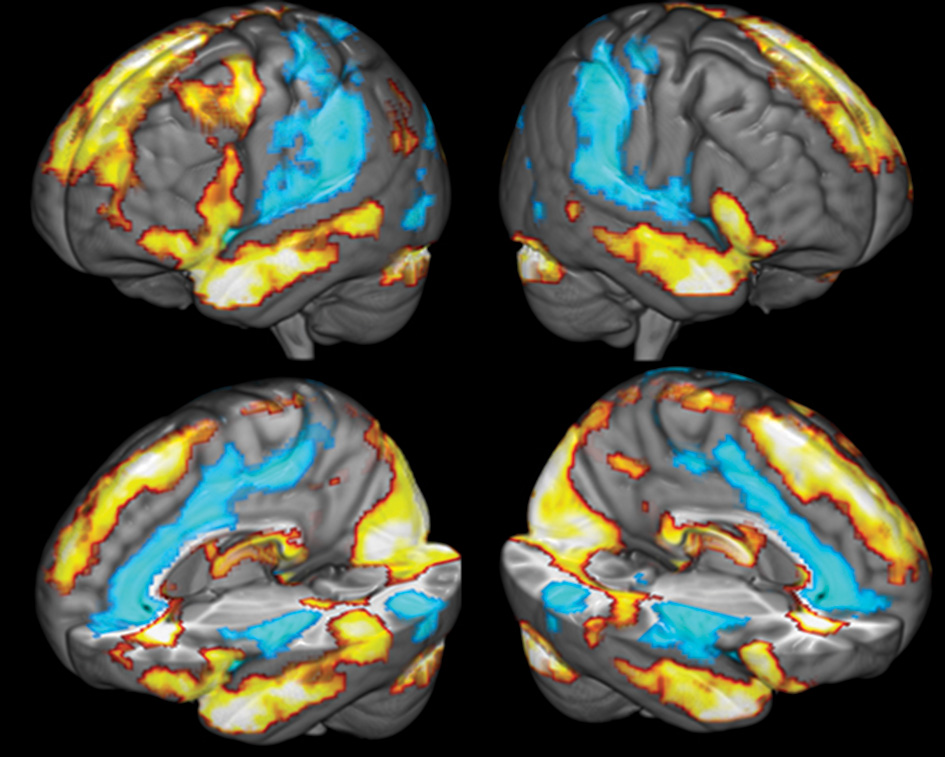

Brain activity was first measured by comparing BOLD activity during the reflection period to baseline to assess participants' general response to the stimuli. The regions positively active during the reflection period, compared to baseline, included the right occipital cortex, the left superior frontal gyrus, the left and right caudate, the left and right temporal pole, the thalamus, the left superior temporal sulcus and the left middle frontal gyrus. Regions that were deactivated included the left and right posterior insula, the right superior temporal gyrus, the perigenual ACC, the right PCC and the left and right middle temporal gyrus (see Figure 4 and Table 2).

Figure 4

Comparison of brain activity during the reflection period to baseline. Yellow colors covering the temporal lobes and superior frontal cortex indicate areas positively associated with the reflection predictor function, blue areas covering the ACC, the insula and secondary somatosensory cortices are negatively correlated with the reflection predictor.